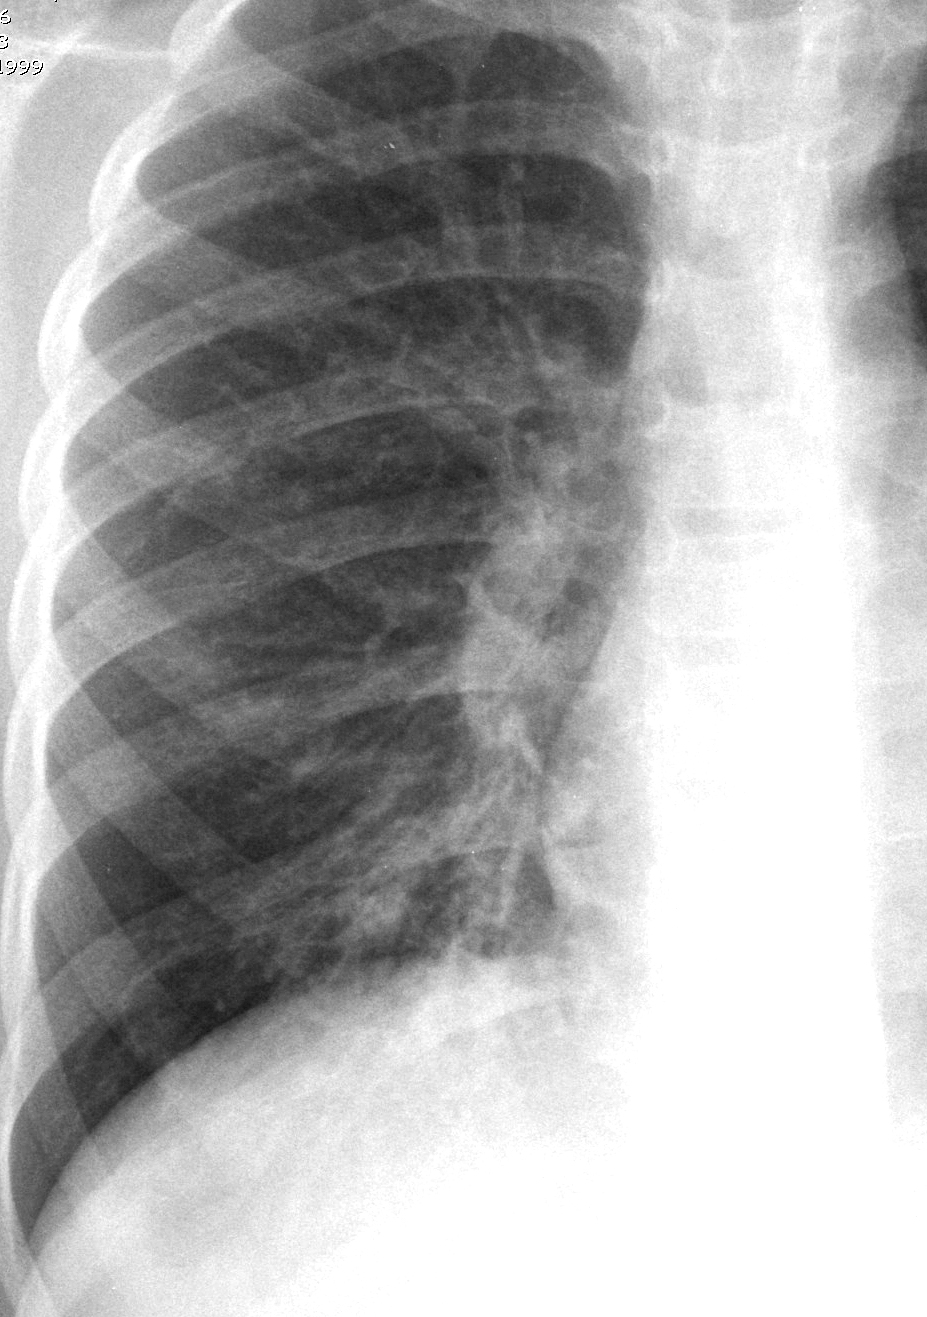

Рентгенодиагностика бронхопневмонии: Советы и примеры

Раздел: Альбом открытий